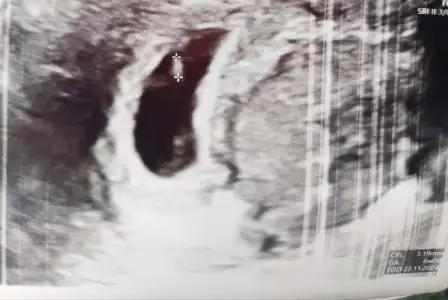

Canım buralardaysan bi tahmin isterim ☺️ Gerçi kalp atışı 90-100 arası, biraz düşük gibi, yine moralsizim, inşallah yükselir 😔 melegim can melegim can

Bu arada karından ultrason.

Karından ise erkek gibi canım ama yinede belli

Olmaz ortada duruyor. Doktoe mu dedi kalp atışı düşük diye bi sıkıntı mı var 100 çokta düşük degil aslında. İnşallah saglıkla ilerler bi sıkıntı çıkmaz canım

Üniversite hastanesinde duyulamadi dediler, eski özel doktoruma gittim, o da 90-100 arası dedi, küçük olduğu için normal dedi ama bana düşük gibi geldi, içime bi kurt düştü, hayırlısı inşallah 🤲